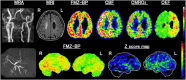

As a sequel of brain ischemia, selective neuronal loss (SNL)-as opposed to pannecrosis (i.e. infarction)-is attracting growing interest, particularly because it is now detectable in vivo. In acute stroke, SNL may affect the salvaged penumbra and hamper functional recovery following reperfusion. Rodent occlusion models can generate SNL predominantly in the striatum or cortex, showing that it can affect behavior for weeks despite normal magnetic resonance imaging. In humans, SNL in the salvaged penumbra has been documented in vivo mainly using positron emission tomography and (11)C-flumazenil, a neuronal tracer validated against immunohistochemistry in rodent stroke models. Cortical SNL has also been documented using this approach in chronic carotid disease in association with misery perfusion and behavioral deficits, suggesting that it can result from chronic or unstable hemodynamic compromise. Given these consequences, SNL may constitute a novel therapeutic target. Selective neuronal loss may also develop at sites remote from infarcts, representing secondary 'exofocal' phenomena akin to degeneration, potentially related to poststroke behavioral or mood impairments again amenable to therapy. Further work should aim to better characterize the time course, behavioral consequences-including the impact on neurological recovery and contribution to vascular cognitive impairment-association with possible causal processes such as microglial activation, and preventability of SNL.